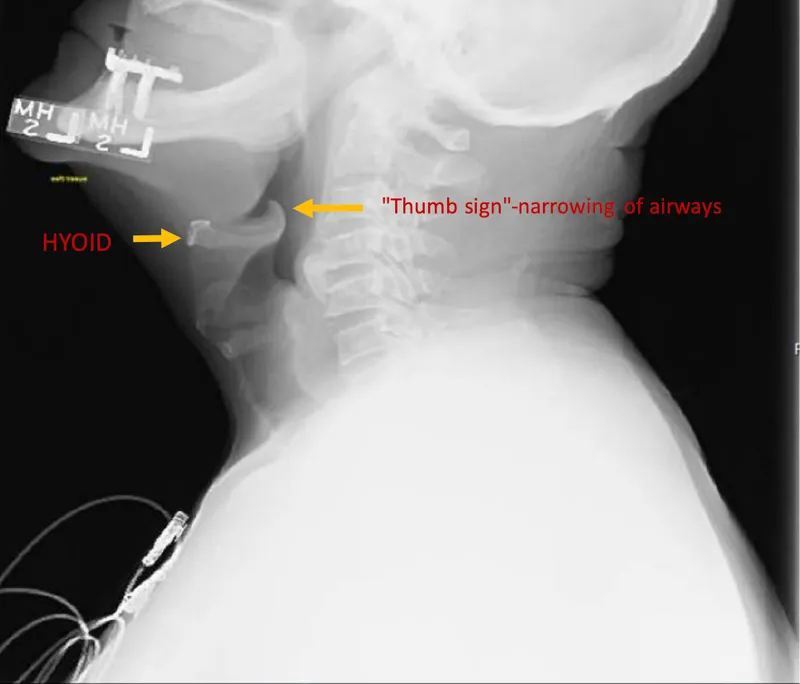

- Lateral Neck X-ray:

- Classic 'thumb sign' (swollen epiglottis).

- Thickened aryepiglottic folds, obliterated vallecula.

- Key Sign: Thumbprint sign on lateral neck X-ray is characteristic.